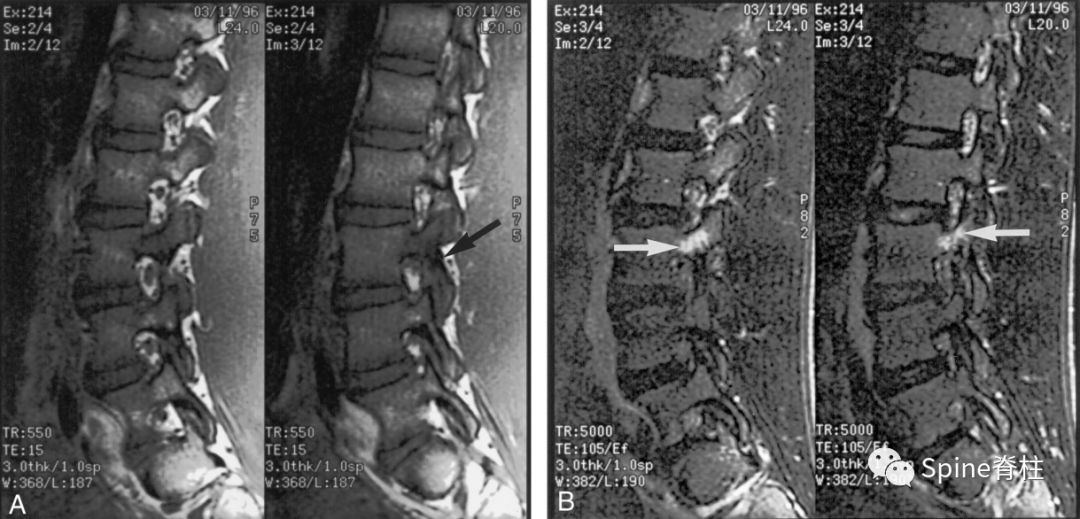

16岁的足球运动员诉右腰部疼痛。A:右侧T1加权像可见腰5峡部和椎弓根呈低信号(箭头);B:右侧T2加权像可见腰5峡部、椎弓根和关节突呈高信号(箭头)。

图:T2水肿信号且峡部皮质不连续断裂

提示L3左侧峡部裂(2级)

17岁的篮球运动员诉腰痛。A:T1像,左侧腰3峡部呈不连续的低信号(箭头);B:T2像,左侧腰3椎弓根和峡部呈高信号(箭头)